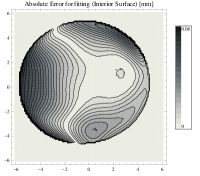

Mean fitting errors for interior and exterior surfaces are respectively and and squared eccentricities are and . The interior surface is thus slightly prolate while exterior is oblate. It is evident that deviations from circular shape are very minute. The magnitude of absolute fitting error is shown on Fig. 3.